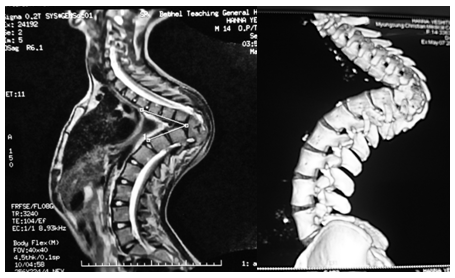

An MRI did not show any spinal cord anomaly but was significant for severe draping of the cord at the apex of the deformity (Figure 6). A CT scan with 3 dimensional reconstruction further detailed the degree of the deformity (Figure 7).

Figure 6 Full Spine MRI Scan.

Figure 7 Thoraco-Lumbar Spine CT Scan with 3D Reconstruction.